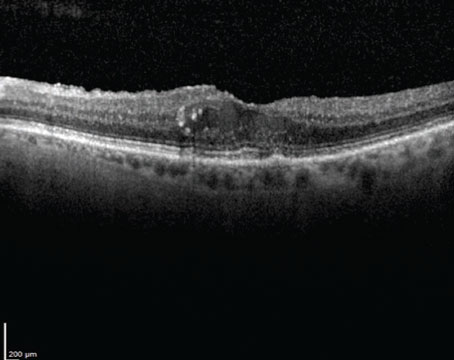

Is drier better in neovascular AMD?

It may depend on the location of the fluid. A quick look at HARBOR post-hoc results.